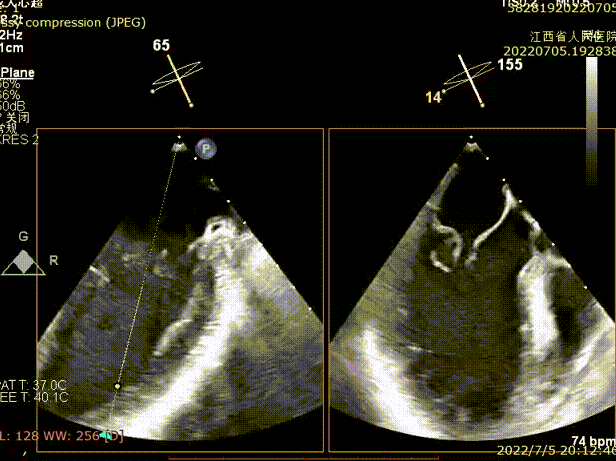

术前经胸超声显示

左心增大,余房室腔大小正常,二尖瓣后瓣于收缩期脱向左房(主要累及2区),对合不良,关闭不佳,二尖瓣部分连接腱索呈连枷样改变, 三尖瓣少量反流,主动脉瓣微量反流,EF 60%;

经食道超声显示(术前):二尖瓣前叶长度26.5mm,后叶长度26mm,脱垂高度9.5mm,脱垂宽度为14.6mm, MVA>4.0cm²;

诊断:二尖瓣重度关闭不全,考虑DMR。

术前TEE显示二尖瓣重度反流,反流位置位于A2/P2区